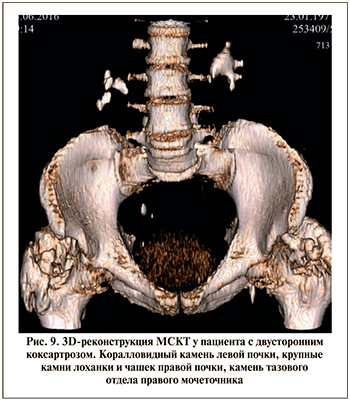

Клиническое наблюдение 5. Пациент В. 55 лет. В анамнезе у больного геморрагический инсульт, осложненный тетрапарезом и формированием стойких контрактур коленных и тазобедренных суставов с исходом в двусторонний коксартроз (рис. 9).

Поступил в урологическое отделение с двусторонним коралловидным нефролитиазом и камнем правого мочеточника. В положении больного на спине выполнена ПНЛТ по поводу камней лоханки правой почки, затем «гибкая» антеградная уретеролитотрипсия, установка внутреннего мочеточникового стента в ходе одной операции (рис. 10).